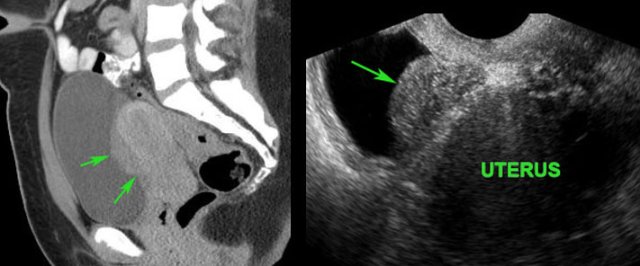

Spontaneous evacuation of postoperative Douglas abscess to rectum. Spontaneous evacuation of postoperative Douglas abscess to rectum.

Deep pelvic abscess

Young woman with abdominal pain and fever 10 days after surgery for perforated appendicitis.

CT shows a bilobar puscollection, close to the thick-walled, empty rectum (R.).

TVUS confirms the abscess, and demonstrates an echolucent tract (*) from the abscess towards the rectal lumen (R.)  with focal blurring of the layer structure of the oedematous rectal wall.

These TVUS findings, in combination with the improving symptoms of the patient, are signs of impending spontaneous evacuation.

Three days later the thick-walled abscess is almost empty.

The patient recovered without surgical or radiological drainage.